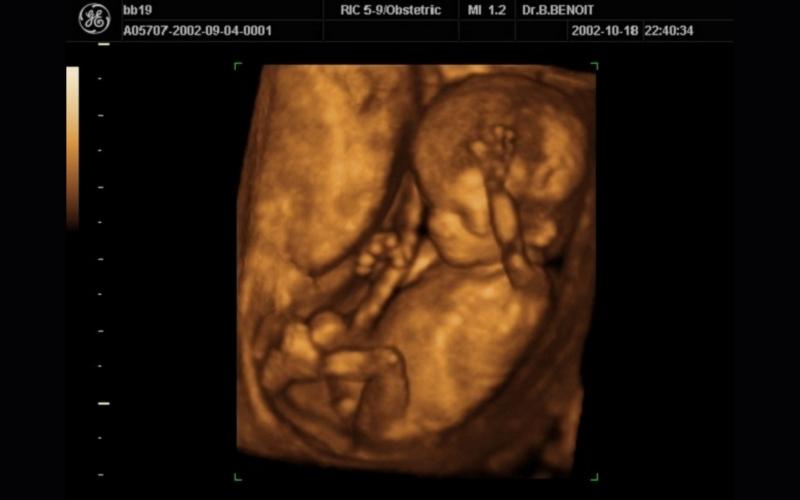

Thai nhi tuần 16 của thai kỳ bắt đầu phát triển các cơ ở khu vực lưng và xương sống, nhờ đó khiến đầu và cổ của thai nhi có thể ngẩng thẳng hơn. Mắt của bé con lúc này có thể chuyển động từ từ, tai cũng bắt đầu hoàn thiện, các xương nhỏ trong tai dần hoạt động giúp thai nhi có thể cảm nhận âm thanh.

Tứ chi của thai nhi có khả năng chuyển động cùng nhau nhưng những vận động này còn quá nhỏ nên thai phụ sẽ khó cảm nhận được. Thai nhi 16 tuần tuổi nặng khoảng 146 g và dài khoảng 14.6 cm .

Vào thời điểm thai nhi 16 tuổi, bộ phận sinh dục đã phát triển rõ rệt. Bác sĩ có thể nhận thấy giới tính của em bé dựa vào hình ảnh siêu âm 4D. Tuy nhiên, tỷ lệ nhận biết chỉ khoảng 80% vì nó còn phụ thuộc vào tư thế nằm của thai nhi, nếu thai nhi nằm sấp sẽ khó phát hiện hơn nhiều.